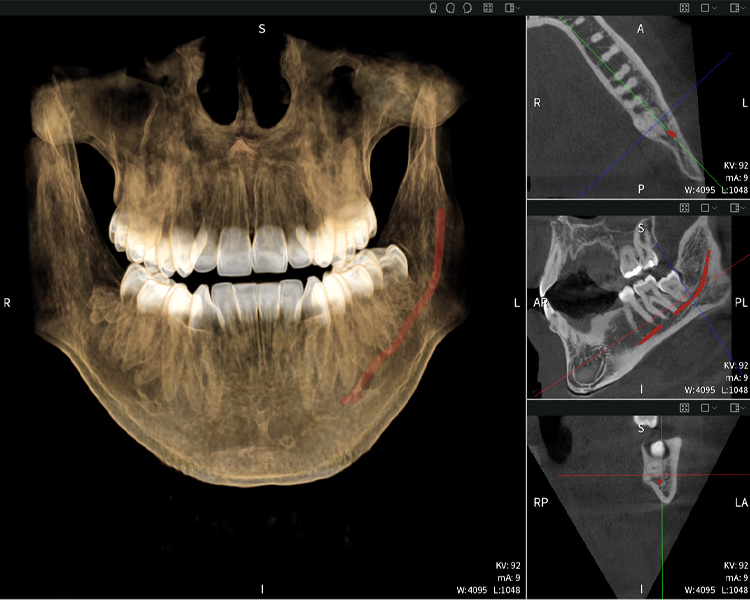

Nachstehend finden Sie einen Fall von Dr. med. dent. Oliver A. Centrella, in dem die CBCT-Aufnahmen mit Seethrough Max entscheidende Informationen zur komplexen Anatomie sowie zur kritischen Beziehung zwischen den Weisheitszähnen und dem Nervus alveolaris inferior lieferten. Bei diesem Fall besteht eine Indikation zur chirurgischen Entfernung der Weisheitszähne.

Abbildung a

- Oben links: Axiale Schnittansicht des linken Unterkiefers (Region 38) mit Darstellung des Nervus alveolaris inferior (rot) in unmittelbarer Nähe zu den Wurzeln des Zahns 38.

- Oben rechts: 3D-Rekonstruktion des gesamten Unterkiefers zur Orientierung. Der rot markierte Nervus alveolaris inferior verdeutlicht seine Lage im Kieferknochen.

- Unten links: Sagittale Ansicht des Unterkiefers (Region 38), die die enge räumliche Beziehung zwischen den Wurzeln und dem Nervenkanal verdeutlicht.

- Unten rechts: Koronale Ansicht des Unterkiefers (Region 38) entscheidend für die Beurteilung der räumlichen Lage der Wurzeln zum Nerven.